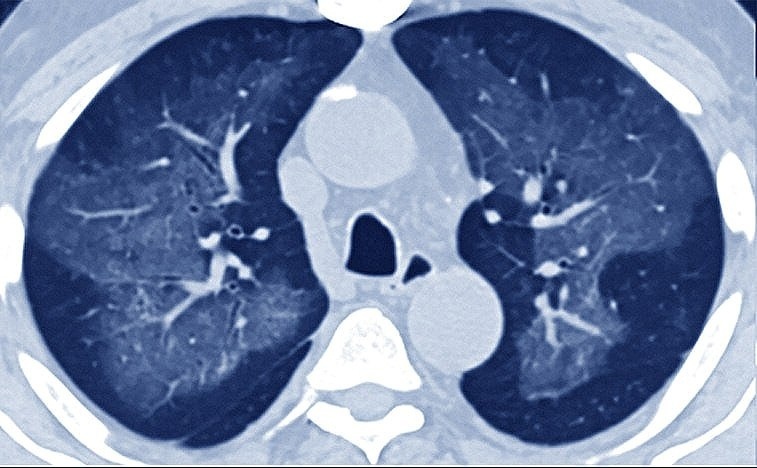

Покажите эту новость курильщику вейпов![]() Что-то на жизненном. Нижегородский Областной диагностический центр показал, как выглядят на КТ лёгкие любителя электронных сигарет и вейпов.

Характерная картина острого повреждения лёгких, до боли знакомый ковидный эффект «матового стекла», как правило, многоочаговый. Дальше это может привести к нарушению просвета бронхов. Бывают и другие клинические маски последствий вредной привычки. Встречаются такие последствия и в 27, и в 40, и в 50 лет. С таким идём прямиком к пульмонологу, если не хотите разучиться дышать. Пар на 95% безопаснее дыма от сигарет, говорите? Источник: Твой Бор